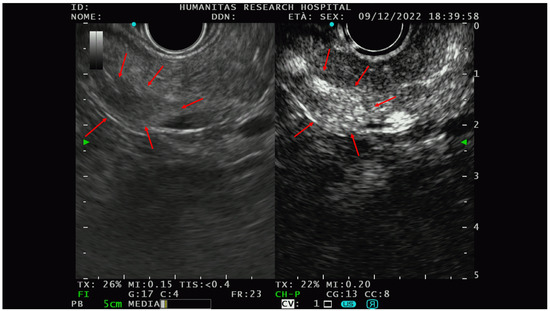

Elastographic characterization has provided different, heterogenous, and sometimes controversial evidence. In 2009, Iglesias-Garcia et al. [41] conducted the first significative prospective analysis on the qualitative elastography pattern of solid pancreatic lesions. They divided the elastography pattern of the lesion of interest in four color regions: from the harder to the softer tissues, they assigned the following colors, respectively: dark blue, green, yellow, and red. All the PNETs diagnosed had a blue pattern at the elastography analysis and all of them were defined as malignant at the pathological analysis. The same group of authors [42] also performed a prospective study with the aim of analyzing the semiquantitative characteristics of PTEN on elastography and they observed that PNET had the highest strain ratio (52.1, CI, 33.96–70.71) among the pancreatic solid lesions including pancreatic adenocarcinoma, chronic pancreatitis, and other inflammatory pancreatic conditions (Figure 2).

Figure 2.

PNET with high lesion-to-parenchyma strain ratio, characterized as G2 with lymphatic invasion at the histological analysis of the surgical specimen.